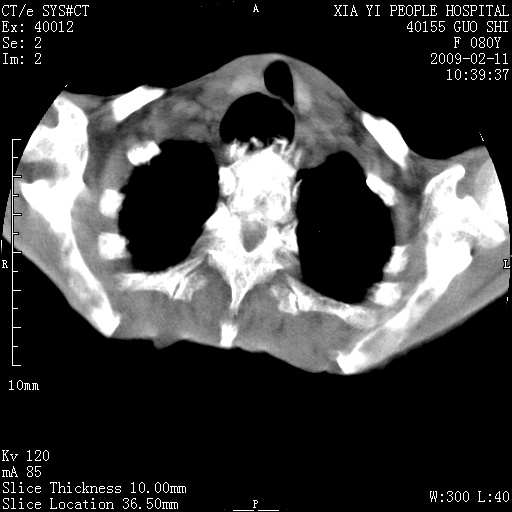

以下是引用随光逐影在2009-2-16 16:34:00的发言:[br]1)考虑右前纵隔皮样囊肿。2)双侧少量胸腔积液。

以下是引用zjzjr在2009-2-16 17:30:00的发言:[br]支持囊性畸胎瘤 双侧少量胸腔积液。